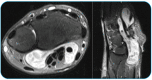

Hydatid Cyst in the Hand